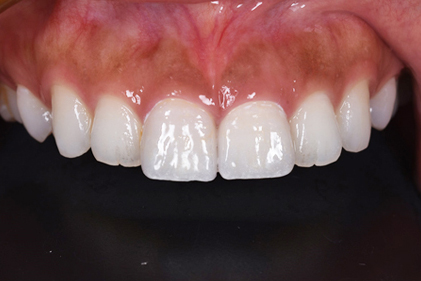

初診時

患者様の主訴は、「前歯の隙間が気になる」

でした。

矯正治療をおすすめしましたが、矯正治療の期間が長いということでセラミック治療を選択することになりました。写真をみるとすきっ歯も気になりますが、以前に詰めたプラスティックも変色して着色しており気になります。

仮歯

セラミックの前に仮歯を調整している段階になります。できればということで歯の長さも短くしたいというリクエストがありましたので、仮歯で調整をしながら様子を見ました。

歯の長さを短くする際に歯を削りますので神経の治療が必要になることがありますので、しみたり・噛んで痛くないか?を約1ヶ月様子を見ました。色・形など仮歯でほぼ問題ないということでしたので、最終的な型採りをしました。

セラミックセット

最終的なジルコニアボンドクラウンをセットしました。すきっ歯がまずなくなりました。また、長かった歯が短くなりましたので本人の希望に沿うことができました。